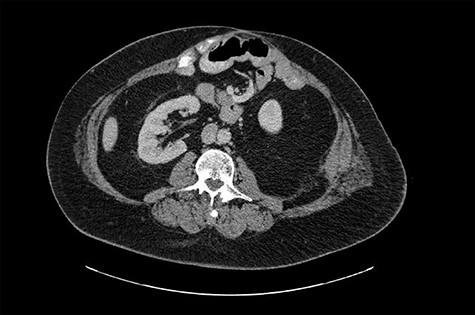

The patient’s past surgical history is very complicated. In February 2015, the patient presented for ischemic colitis with bowel perforation, requiring an exploratory laparotomy that resulted in a subtotal colectomy with end ileostomy. His hospital course was protracted due to wound infections and intra-abdominal abscesses. After 7 months, he presented for an ileostomy reversal and underwent a laparotomy with small bowel resection and ileocolic anastomosis. His hospital course was protracted once again due to an intra-abdominal anastomotic leak and multiple abdominopelvic abscesses. This resulted in a resection of his ileoproctostomy, multiple abdominal washouts, a small bowel resection and creation of an end-ileostomy. In 2016, the patient presented multiple times with a recurrent left retroperitoneal abscess along the posterior abdominal wall and underwent three open abdominal surgeries for incision and drainage. A computed tomography (CT) scan from November 2016 did not show any evidence of kidney herniation (Fig. 1).

Computed tomography (CT) image from 2016 shows the right kidney in normal anatomical position.